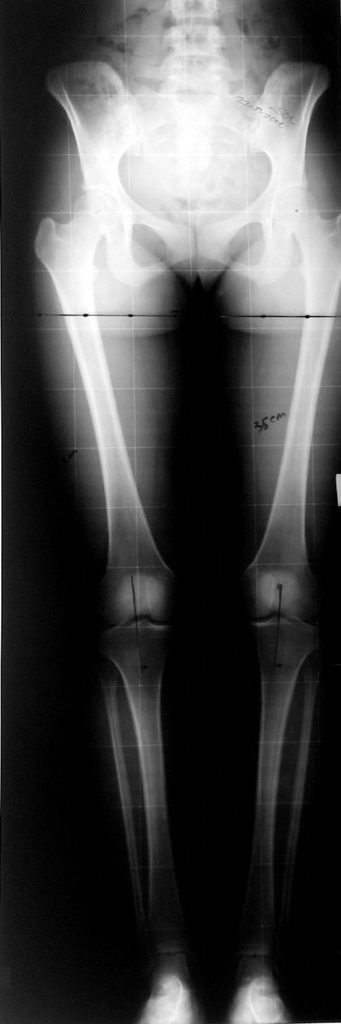

Alt ekstremite (uzuv) uzunluk farklılığı kozmetik bir problem olmaktan öte fonksiyonel ortopedik sorunlara neden olur. Gerek frontal plandaki denge bozukluğuna bağlı yürüme paterni değişiklikleri, gerekse aksiyel iskelette ortaya çıkan dejeneratif bozukluklar nedeni ile ortopedistler bu patolojinin tedavisi ile yakından ilgilidirler.

Günümüzde ekstremite uzatma uygulamaları için tercih edilecek yöntemde aranan en önemli özellikler şöyle sıralanabilir; uygulama süresi, “alignment” (kemiğin anatomik ve mekanik aksı) sağlama , toplam ameliyat sayısı, rejeneratın refraktürden korunabilmesi, çivi dibi infeksiyonu ve sebep olabileceği komplikasyonların asgari miktarda tutulması, hareket açıklığının korunması, “iyileşme zamanı “, günlük hayattaki konfor ve uygulama maliyeti.

Örnek sayılarının az olmasına rağmen etyolojik faktör, yaş, patolojinin yerleşim yeri, miktarı gibi faktörler yönünden benzer iki grubu karşılaştırmayı amaçladık. Eşlik eden tibial uzatma, osteotomi yeri gibi ayrıntıları bu ilk çalışmada göz ardı ettik. Prospektif randomize karşılaştırmalı bioistatistik analiz yapmamız için örnek sayımız azdır. Bu çalışmanın sonuçları matematiksel olarak anlamlı istatistik veriler içermese de belirli bir tecrübenin aktarılması yönünde ülkemizdeki ilk ve tek örnek olduğuna inanıyoruz.